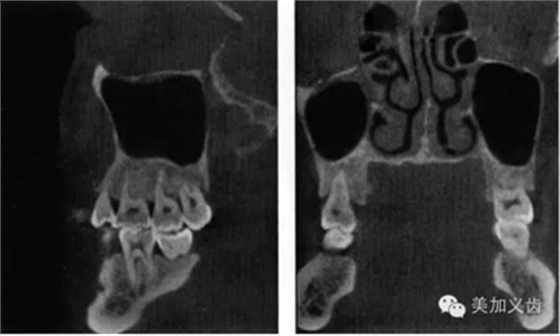

——錐形束CT

這個(gè)是三維放射線重建影像可以全面、準(zhǔn)確的評(píng)價(jià)解剖學(xué)結(jié)構(gòu),包括可用骨形態(tài)的三維數(shù)值,通俗點(diǎn)講就是可以看到可用骨的垂直向、近遠(yuǎn)中向和頰舌向的數(shù)值。

其優(yōu)點(diǎn)是:可以提供精確的、亞毫米級(jí)測(cè)量數(shù)值,與印模結(jié)合,通過(guò)CBCT數(shù)據(jù)來(lái)實(shí)現(xiàn)模擬手術(shù)并制作外科導(dǎo)板。CBCT的放射量與傳統(tǒng)CT相比要小很多,放射時(shí)間短,操作也比較簡(jiǎn)單。